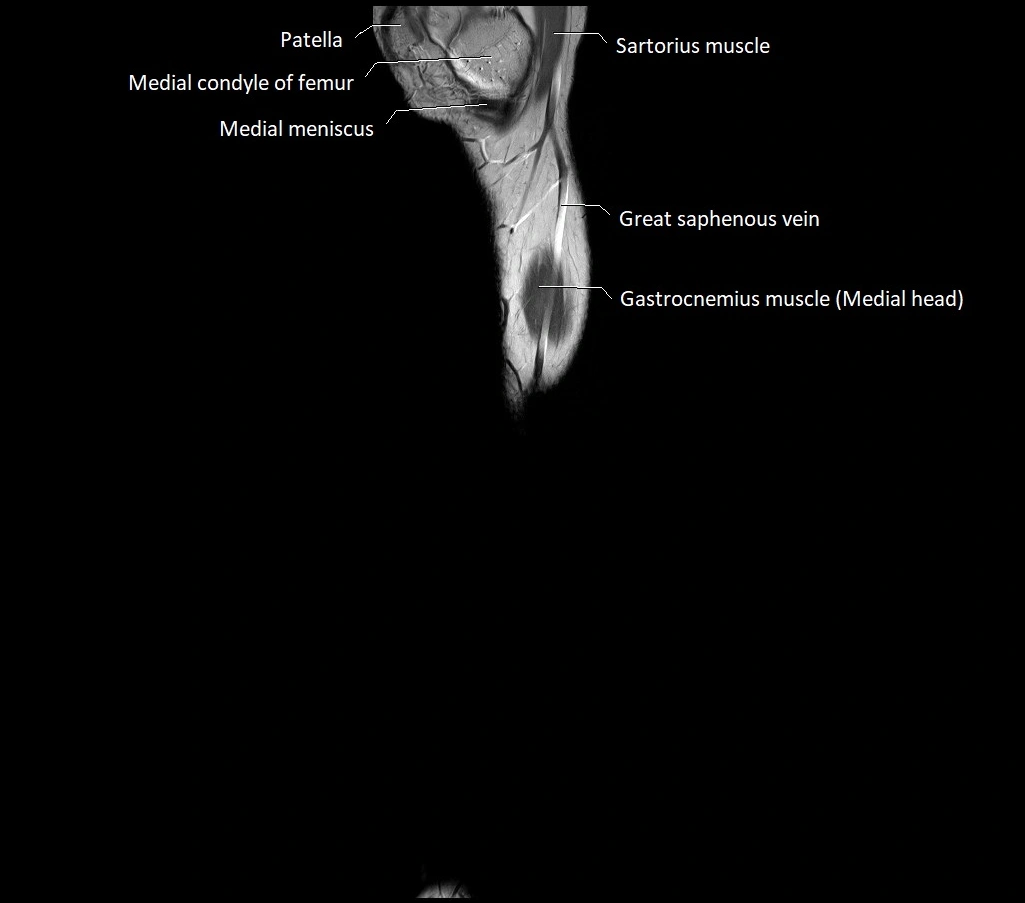

MRI image